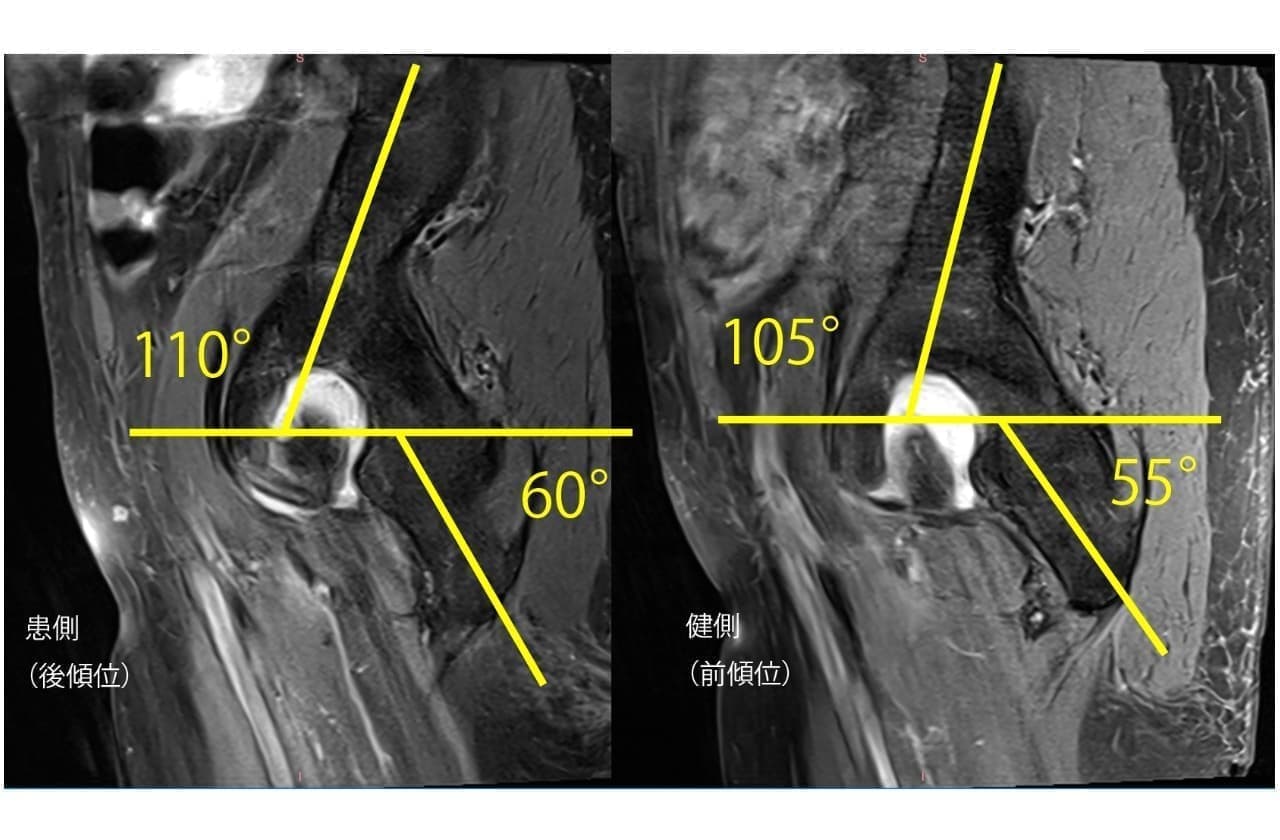

仙腸関節障害とFAI(大腿骨寛骨臼インピンジメント)

大腿骨寛骨臼インピンジメントでは、CAM手術した群と骨盤を10度後傾させた群では、得られる股関節の可動域変化が同等であると言われています。

股関節の付け根(鼠径部)の痛みが誘発されるため、一般的な骨盤後傾トレーニングを行い大腿骨と寛骨の衝突を防ぐのですが、それがきっかけで仙腸関節障害に至る方がいます。